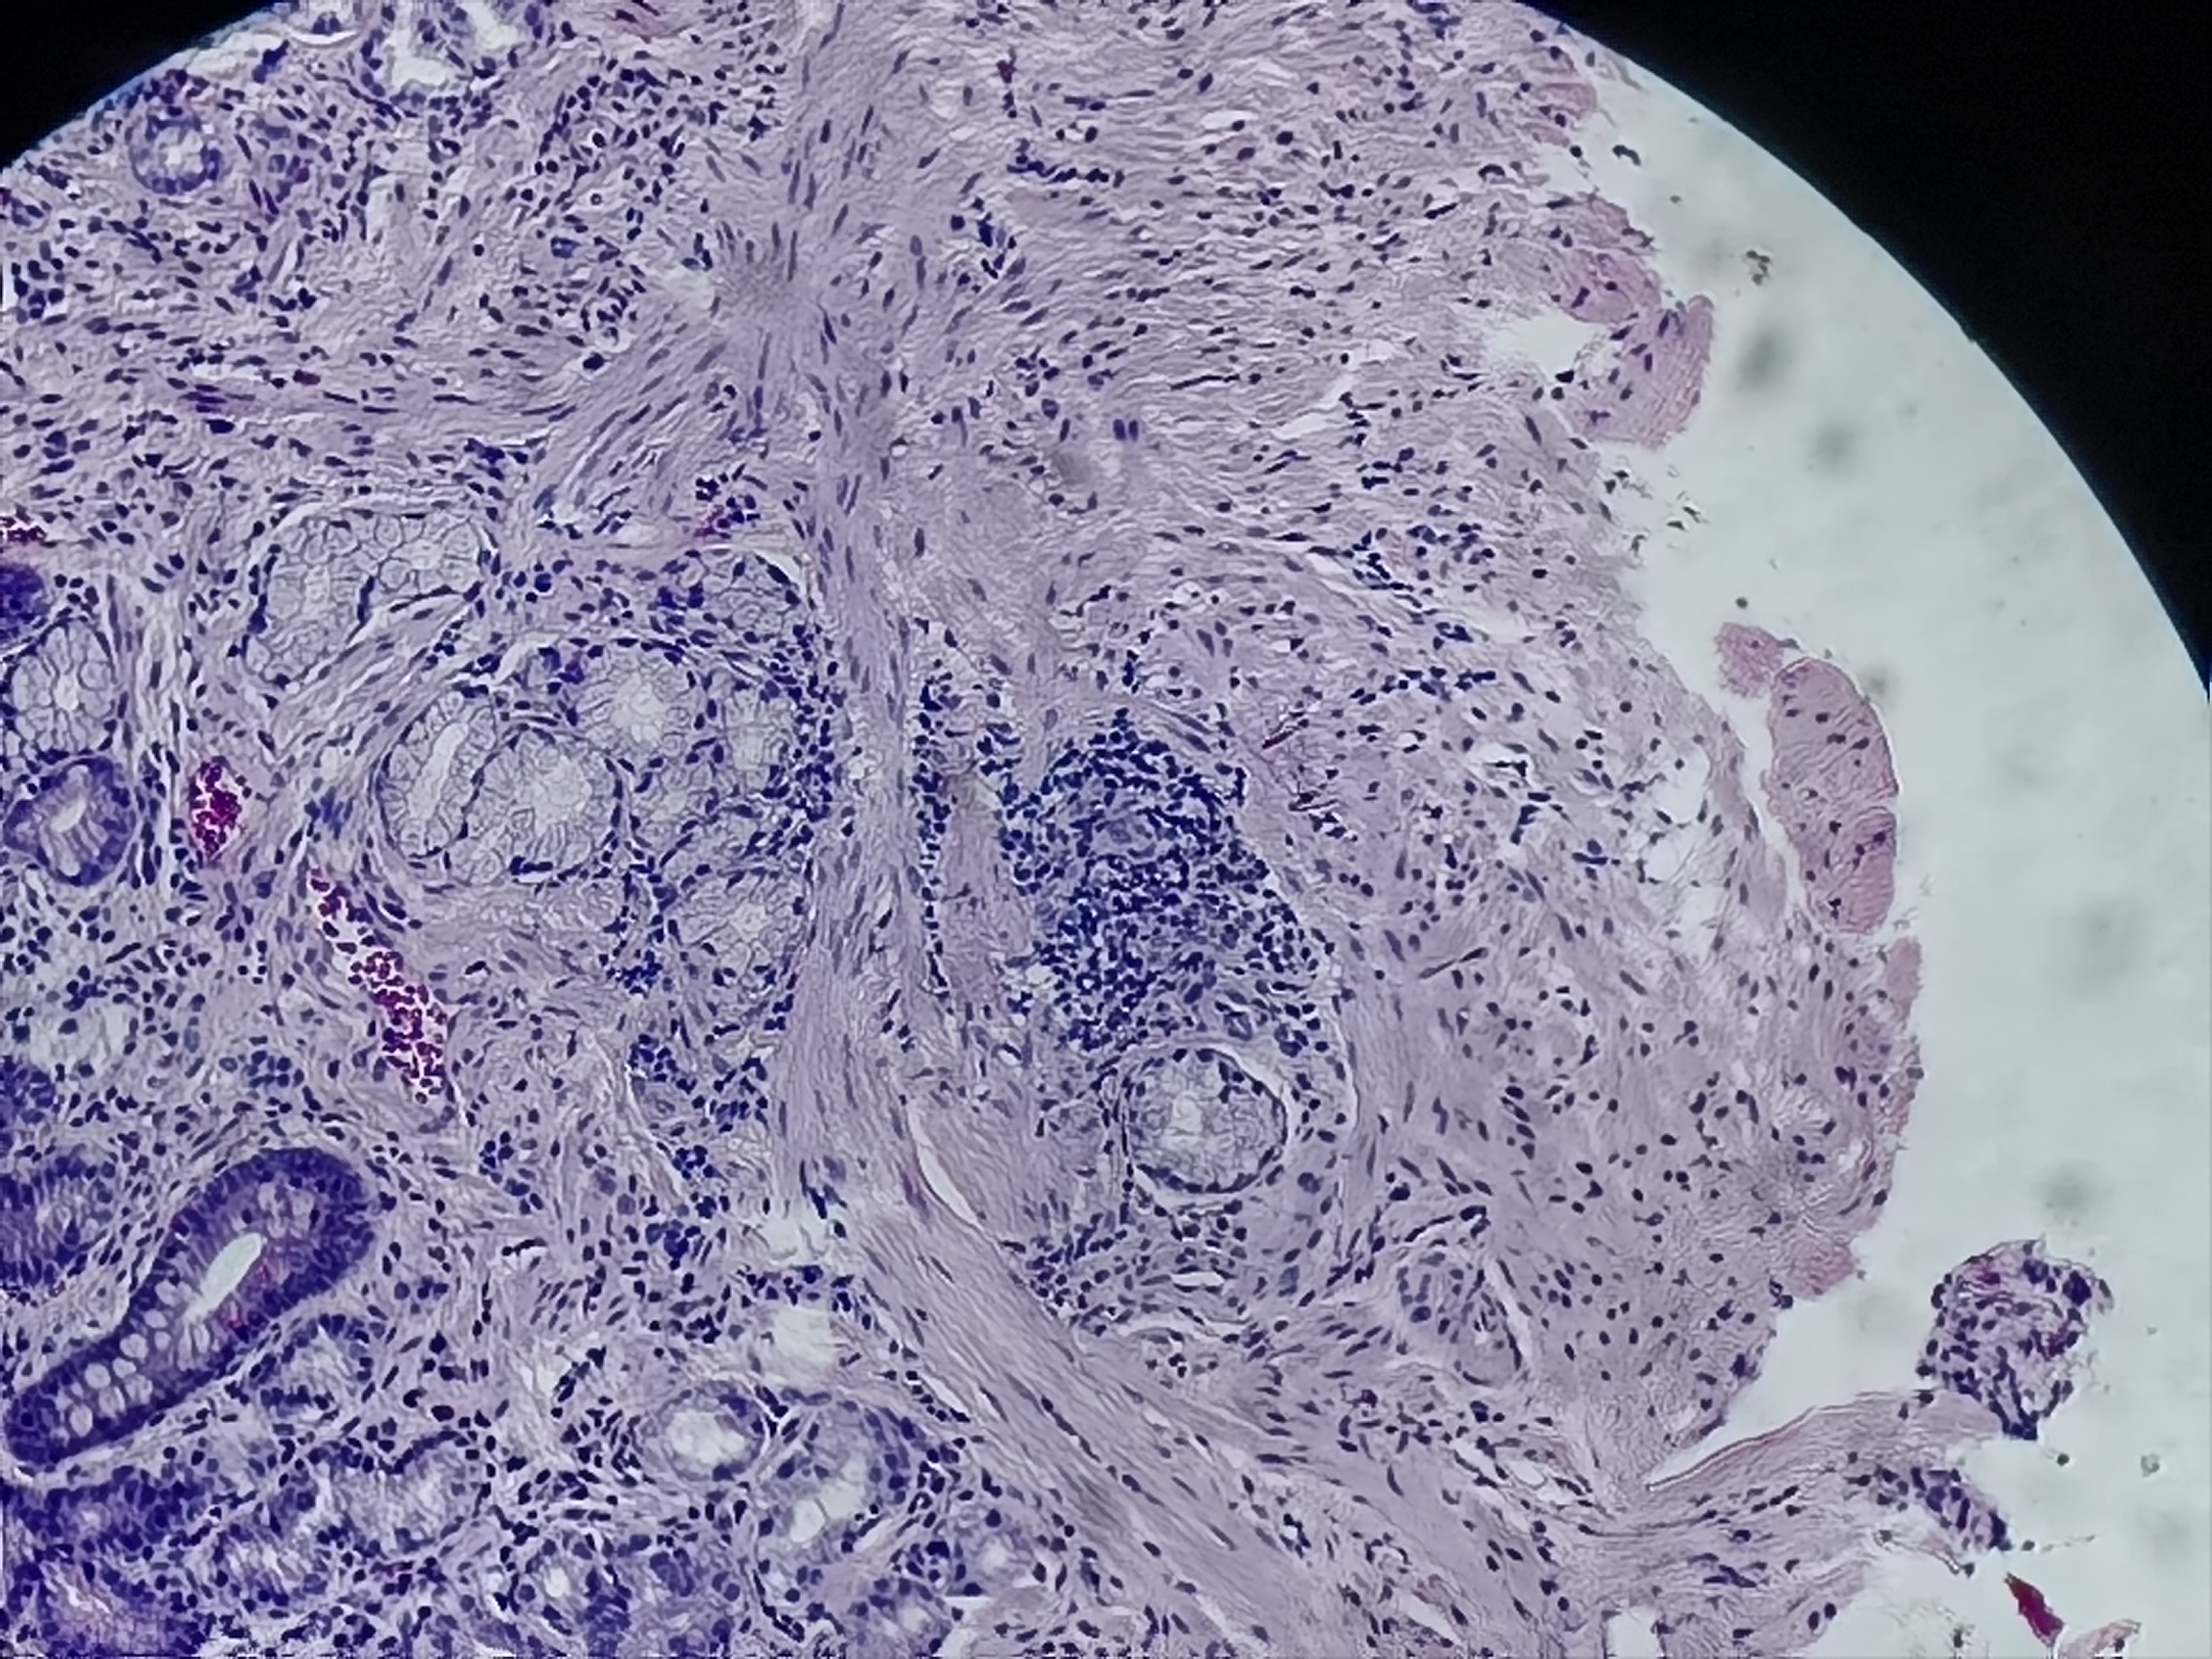

胃体活检

性别

男

年龄

58岁

临床诊断

慢性萎缩性胃炎伴糜烂

一般病史

胃体下部大弯侧粘膜凹陷

标本名称

胃体粘膜活检

大体所见

灰白色组织1块

慢性萎缩性胃炎

中度萎缩+中度肠化+糜烂